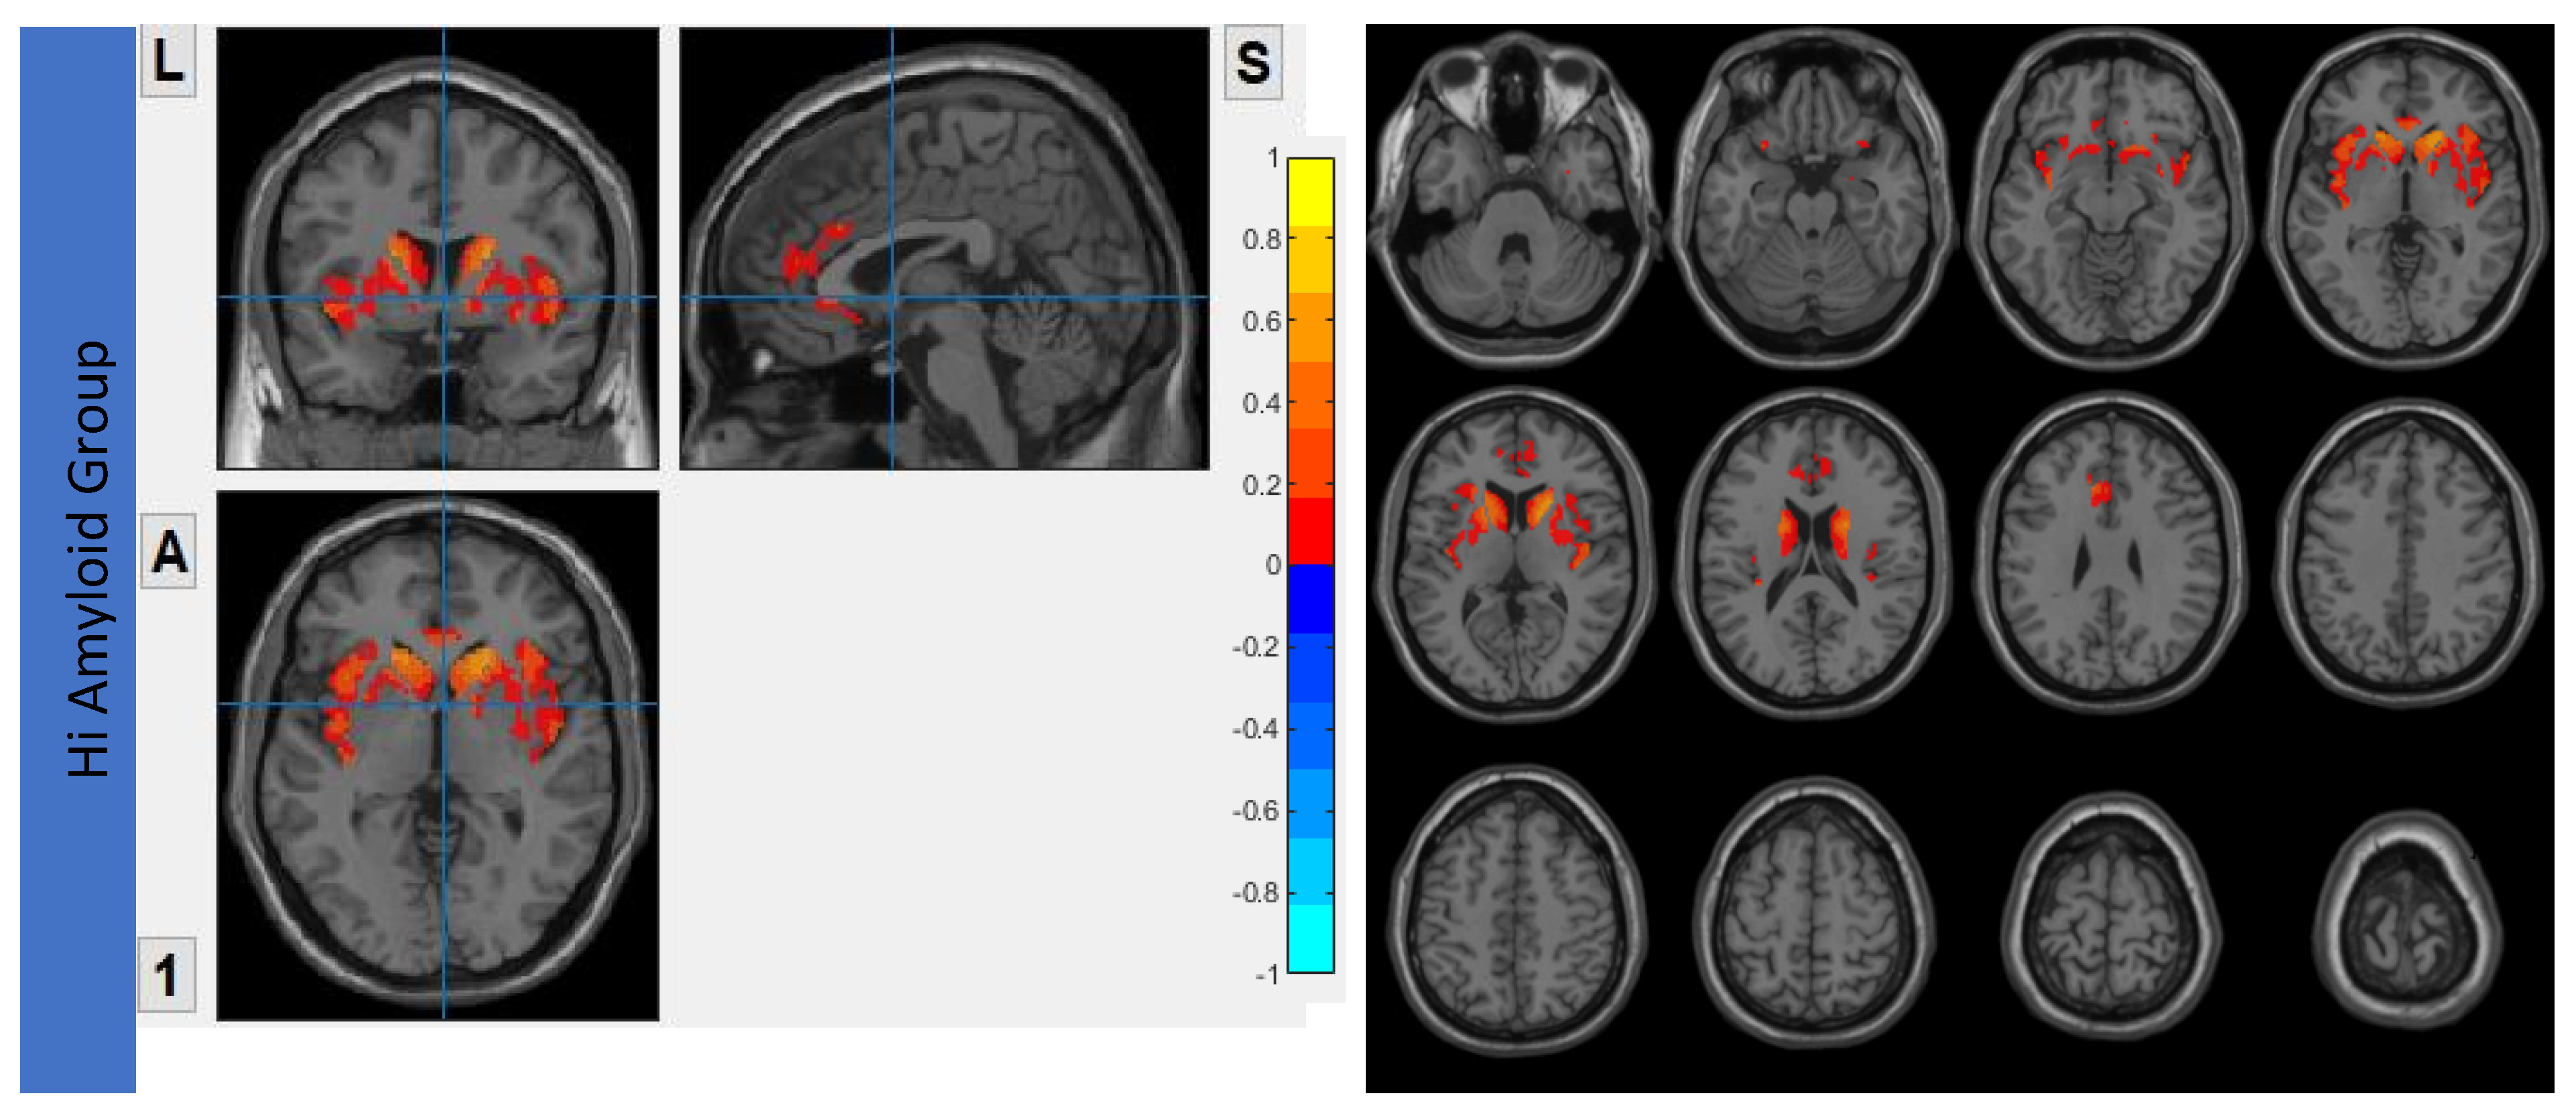

6.3. Interhemispheric Functional Connectivity (VMHC) Maps

7.3. Within SN